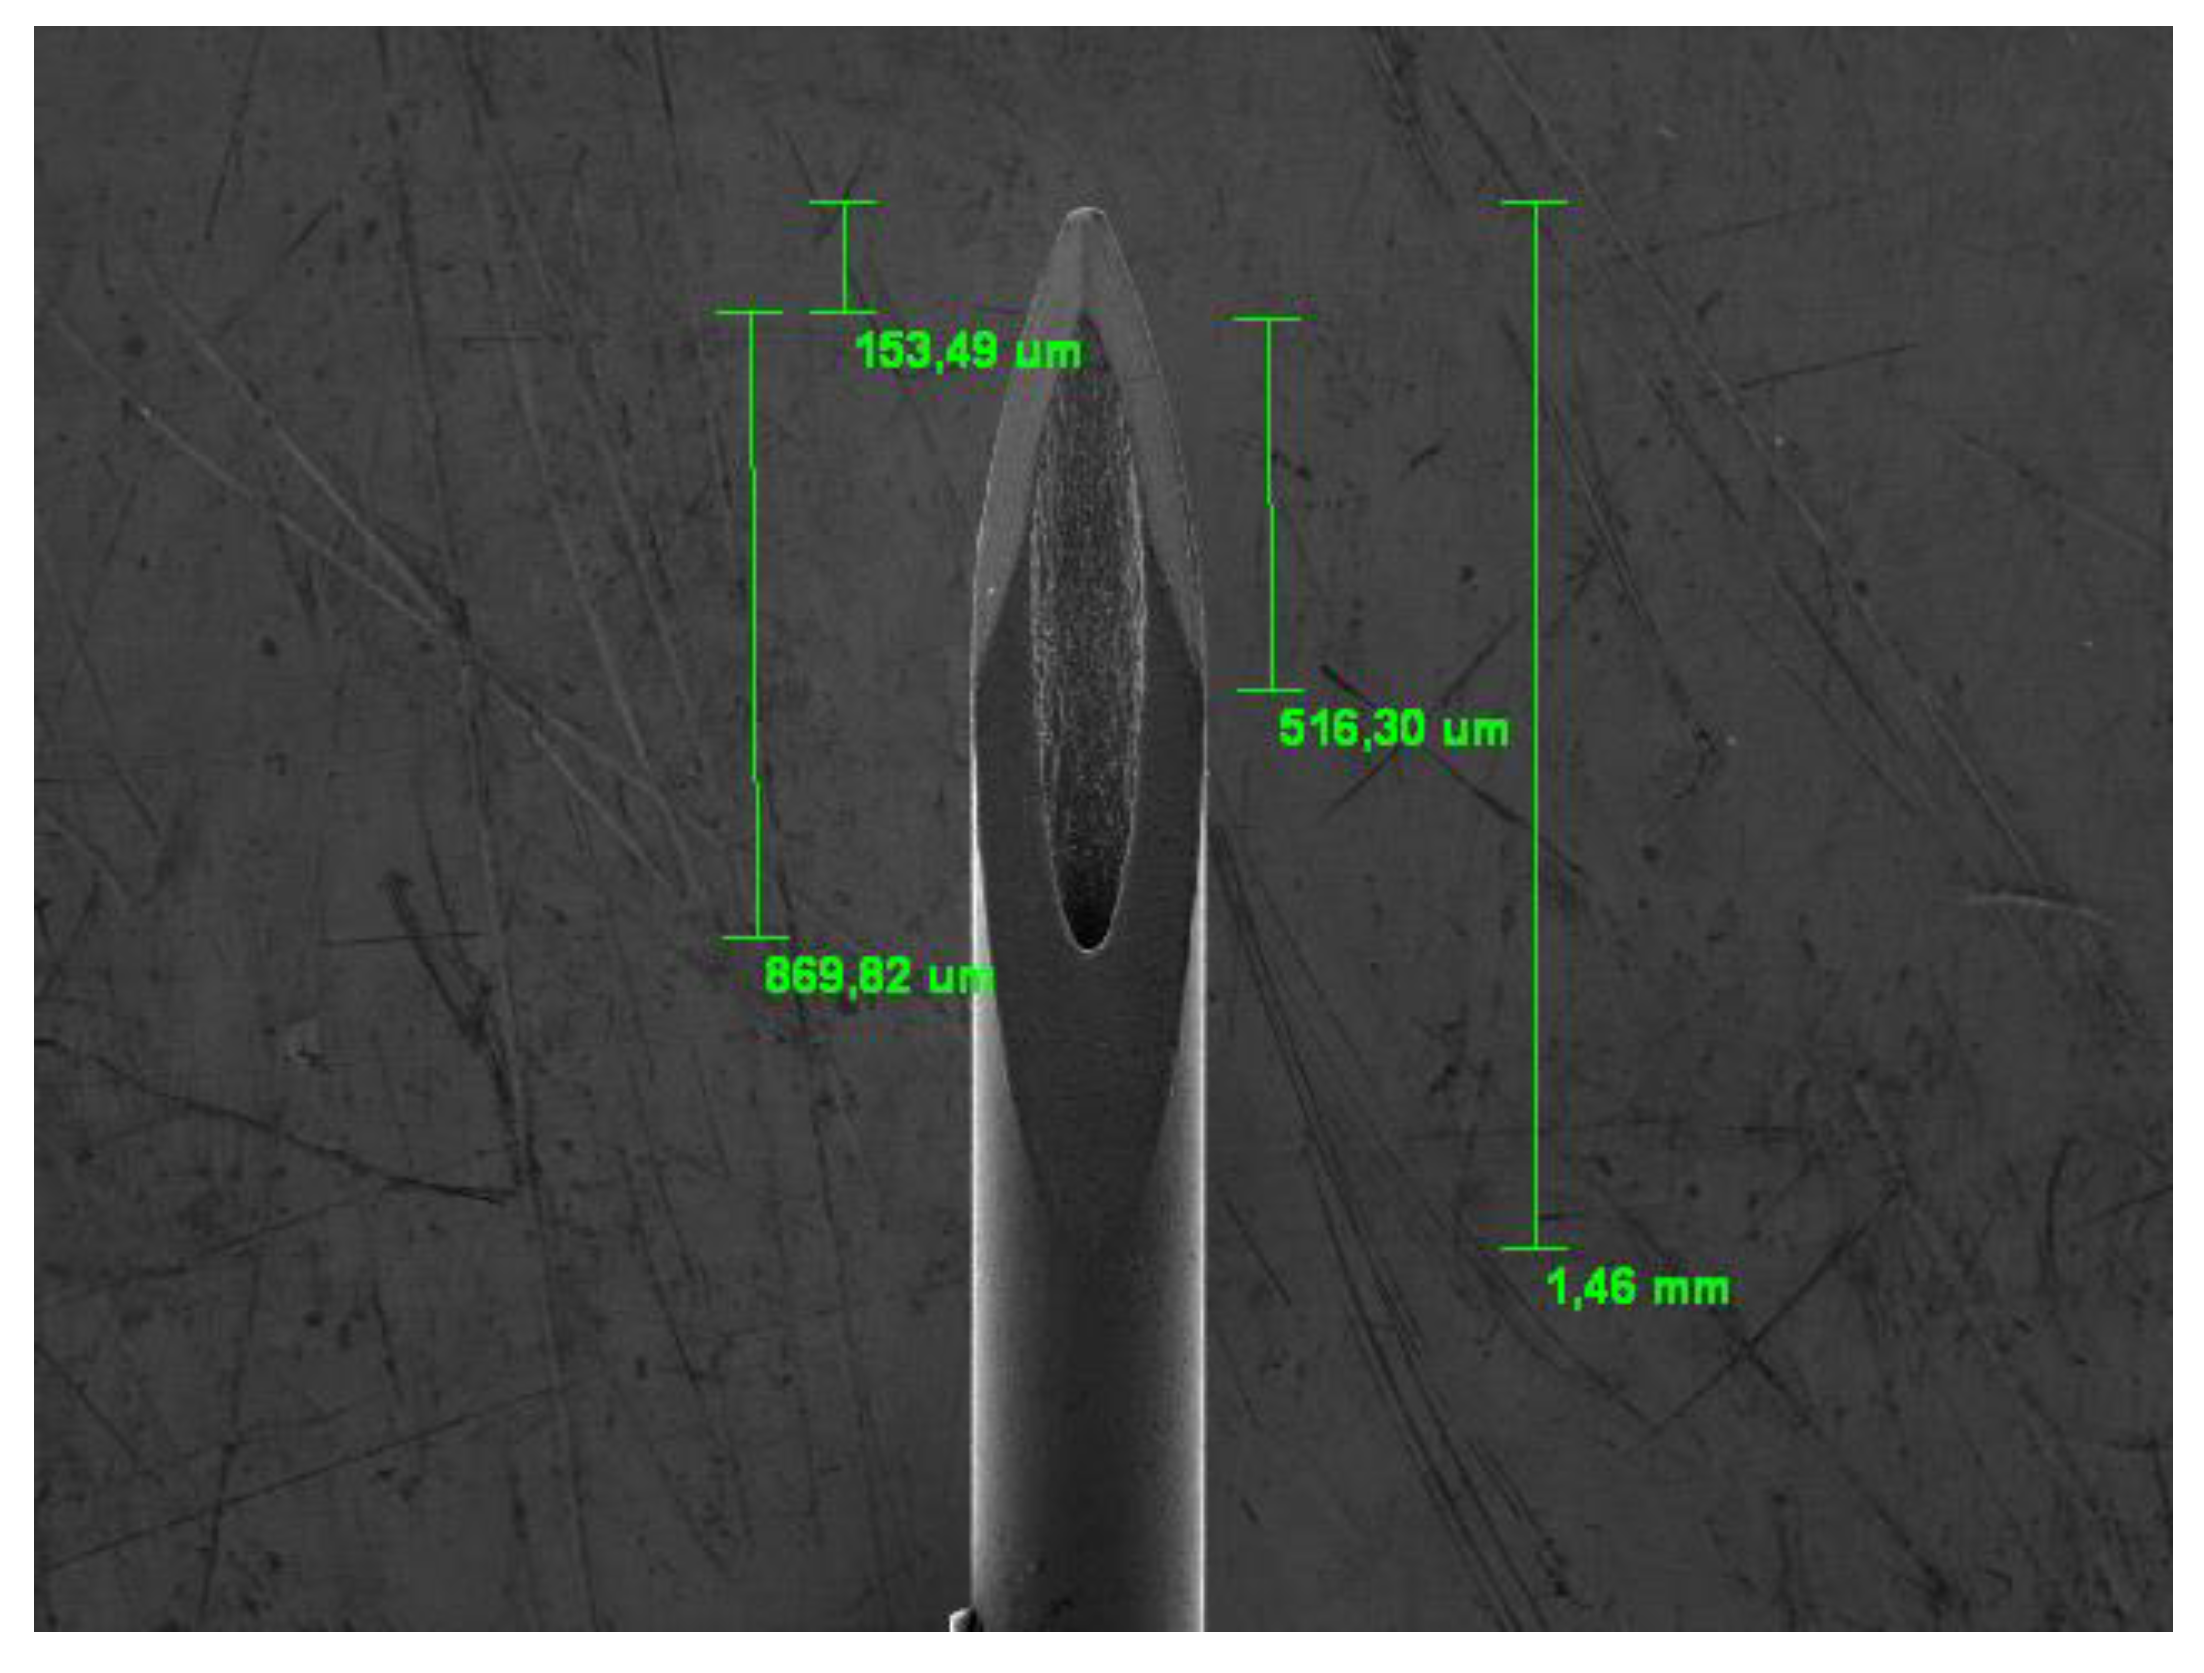

The SEM observation also allowed us to precisely measure some dimensional values ​​of the tested needles to evaluate the homogeneity of the construction dimensional parameters and any differences between groups A and B; in order to carry out this measurement the needles were observed from different observation points. (Figure 4 and Figure 5).

All needles (30G) tested and observed under SEM showed an external diameter of 0.30 mm (+/- 0.03) and an internal diameter of 0.15 mm (+/- 0.04).

Figure 4. Initial measurement of new needles.

Preprints 111024 g004

Figure 5. Measurement of wall thicknesses.

Preprints 111024 g005